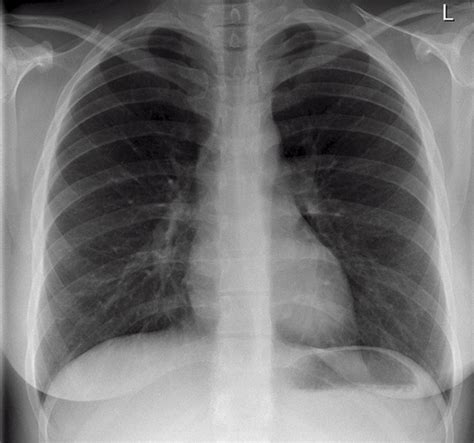

Common Findings in a Normal Chest Ray

A Normal Chest Ray typically reveals the following structures and conditions:

Structure/Condition Description

Lungs Clear lung fields with no signs of infection, inflammation, or tumors.

Heart Normal size and shape, with no signs of enlargement or fluid accumulation.

Ribs and Spine Intact bones with no fractures or abnormalities.

Diaphragm Normal position and movement.

Pleural Space No fluid or air accumulation.

Interpreting a Normal Chest Ray

Interpreting a Normal Chest Ray involves examining the images for any abnormalities. Radiologists look for signs of:

• Lung Conditions: Pneumonia, lung cancer, or emphysema.

• Heart Issues: Enlarged heart, fluid around the heart, or heart failure.

• Bone Abnormalities: Fractures, tumors, or infections in the ribs or spine.

• Other Structures: Enlarged lymph nodes, pleural effusions, or foreign objects.